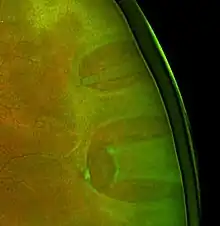

| Ultrasound of a retinal detachment in a patient presenting with complete vision loss and light perception only. | |

Ultrasound, MRI, and CT scan are commonly used to diagnose retinal detachment.